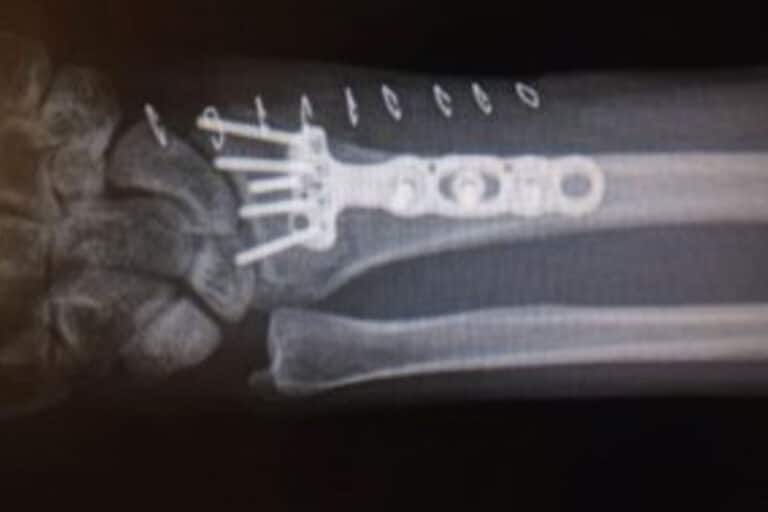

I learned first-hand, or wrist in this case

As an Estate Planning Attorney, I try to always plan for the future. I work with clients to make sure they have a plan in place for every worst-case scenario. These plans include contingencies for personal and financial care, due to a permanent and/or temporary disability, that limits a person’s mental and/or physical capabilities. I…